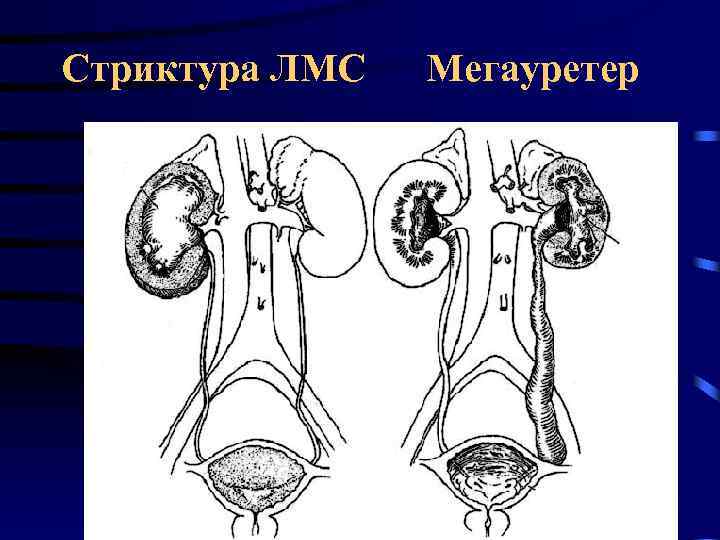

Стриктура ЛМС Мегауретер

Стриктура ЛМС Мегауретер